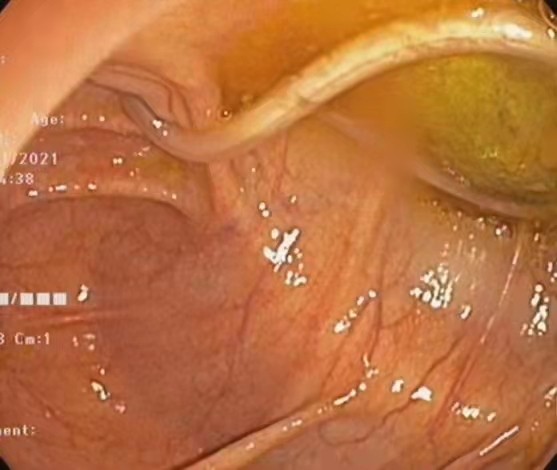

西安莲湖秦华中医医院徐伟医师-内镜下精准取蛔虫!

11月20日下午由徐伟主任为患者闫先生进行肠镜检查,在回盲部发现一条蛔虫,长约20cm,向阑尾开口处蠕动,与患者家属告知病情及沟通后,立即给予异物钳钳夹蛔虫,随镜取出。徐主任表示此次患者行结肠镜检查非常及时,若蛔虫进入阑尾,则患者腹部疼痛剧烈,需住院手术治疗,且肠镜发现蛔虫案例及罕见。患者及家属表示感谢,为徐主任丰富的临床经验点赞。